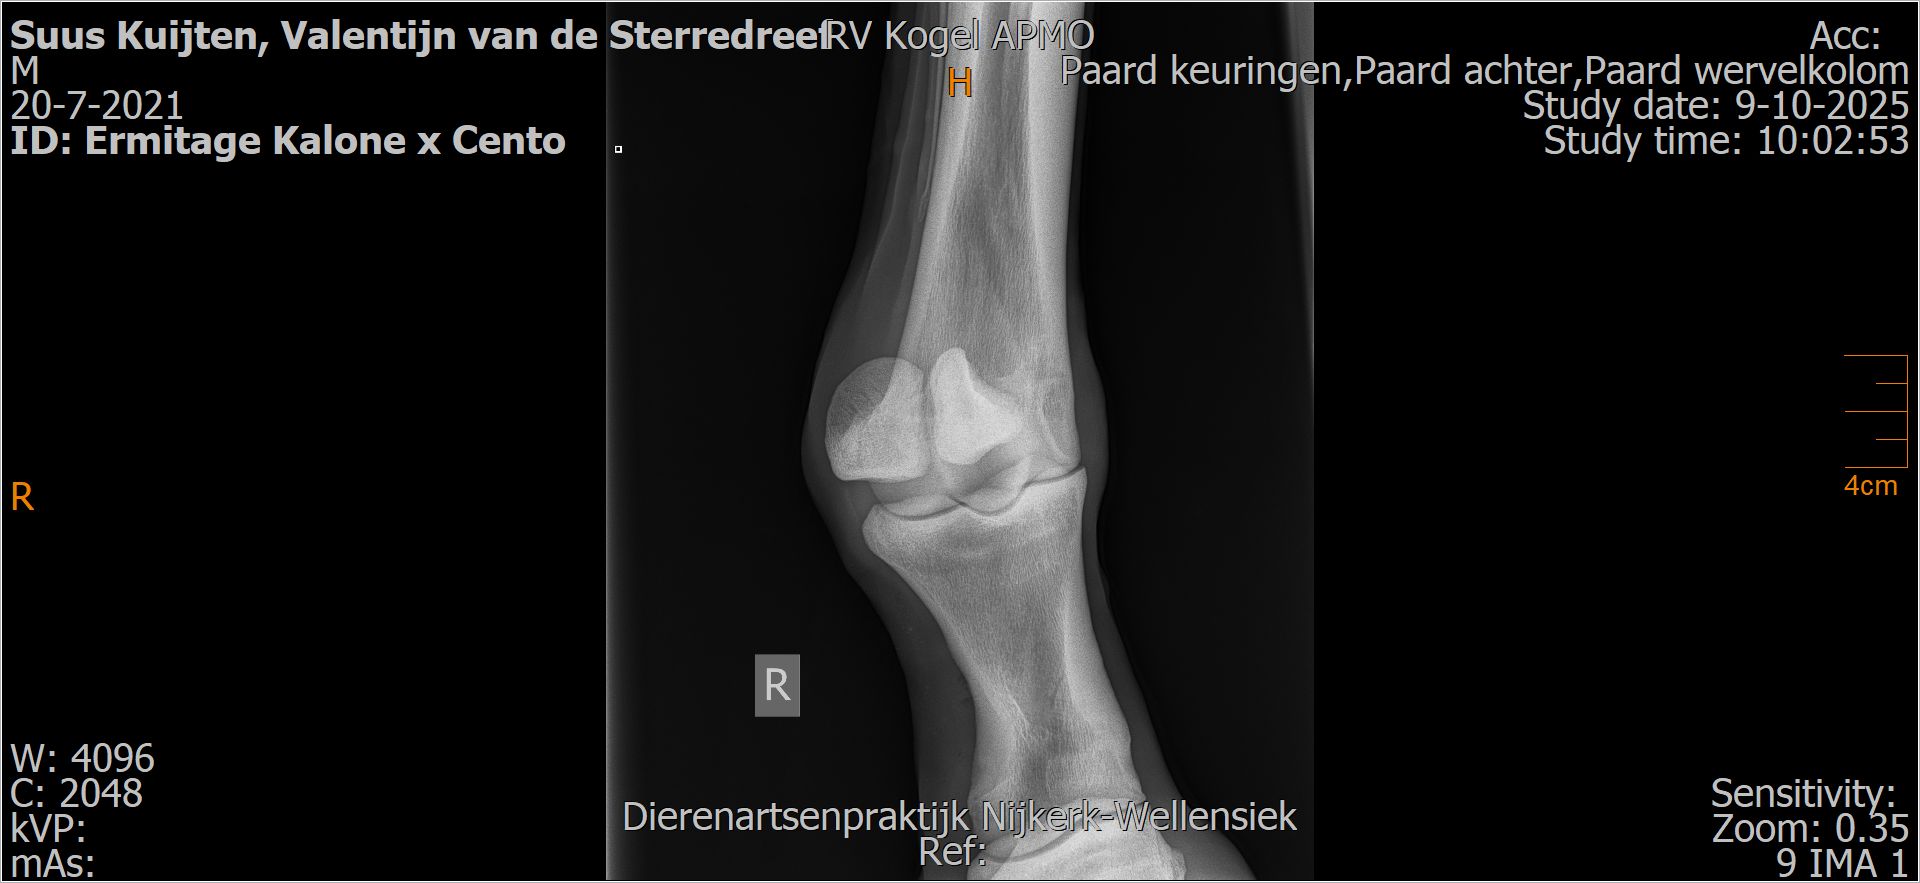

Valentijn van de Sterredreef

Leeftijd:

4

Röntgenfoto’s